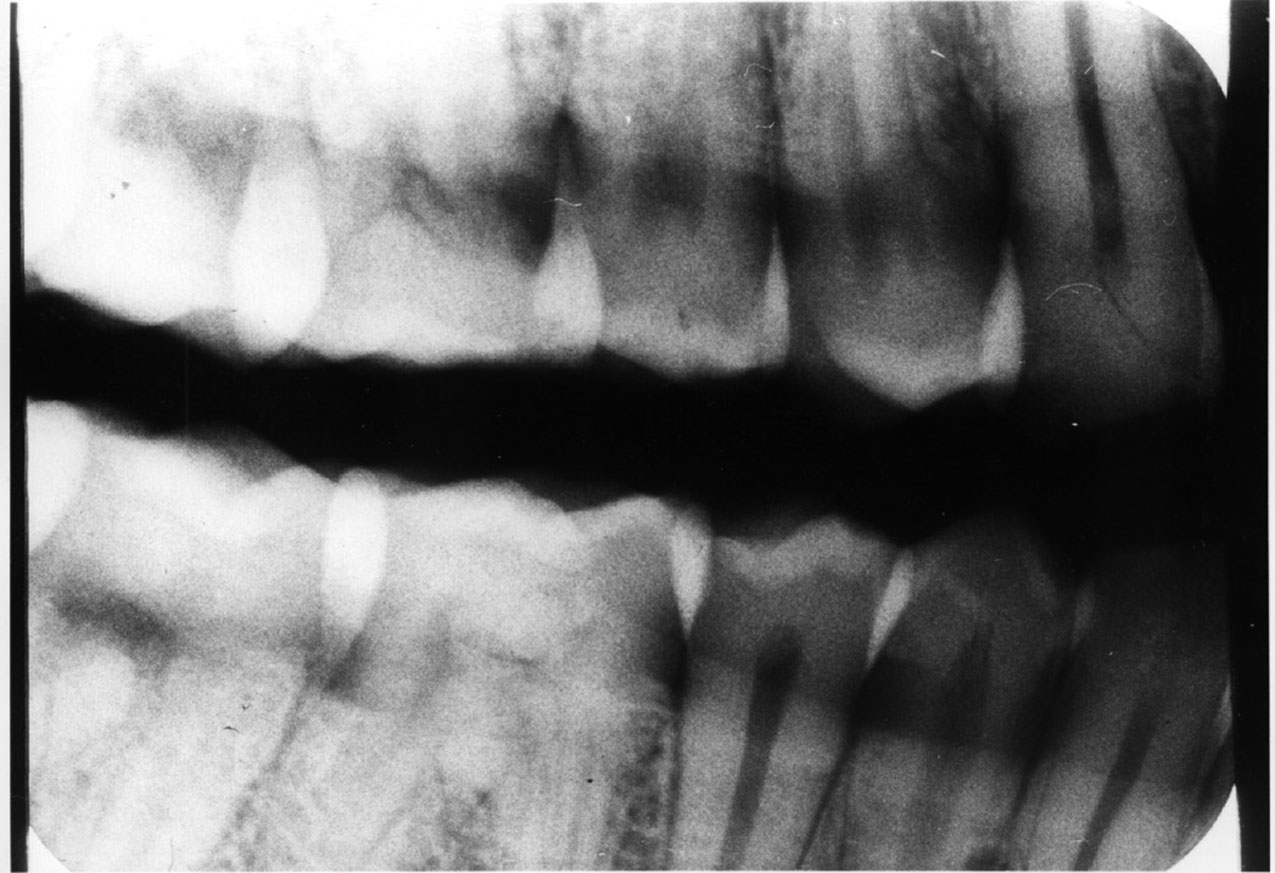

Focal Trough

Panoramic radiographs blur out some anatomic structures in order to detail others. The U-shaped area where the maxilla and mandible are the sharpest is the image layer or focal trough. Image sharpness within the trough is determined by the position of the object in respect to the x-ray source and the film plane as it rotates around the axis or center of rotation. While different x-ray ma­chines have different trough sizes and shapes, there are several general statements that can be made about all panoramic exams: 1) As the size of the focal trough increases, image sharpness decreases. 2) Image magnification and blurred margins increase more rapidly medially than laterally to the focal trough. 3) Trough thickness is directly related to acceptable image blurring. The thicker the trough, the more the image will be blurred.

The focal trough concept is used to prevent superimposition of extraneous structures which would impede clear view of the dental arches, and allow the clinician to view a discrete, selected image field. Unfortunately, one of the disadvantages of this concept is the exclusion of structures that may reveal diagnostically important information. For example, supernumerary teeth or other dental pathosis lying outside the focal trough may not visualize clearly enough for diagnosis.

Conversely, this same panoramic quirk could suggest the presence of a condition that did not really exist. For example, if the apices of the mandibular incisors were missing, as they are in Figure 24, the clinician could suspect external resorption. In this particular case, further examination with selected periapical films confirmed that the patient had normal, pathology-free dentition. The incisal apices had not visualized on the panograph because the operator had positioned the patient slightly too far forward for the apices to fall within the focal trough.

Figure 24. Panoramic error - patient too far forward.

Figure 24